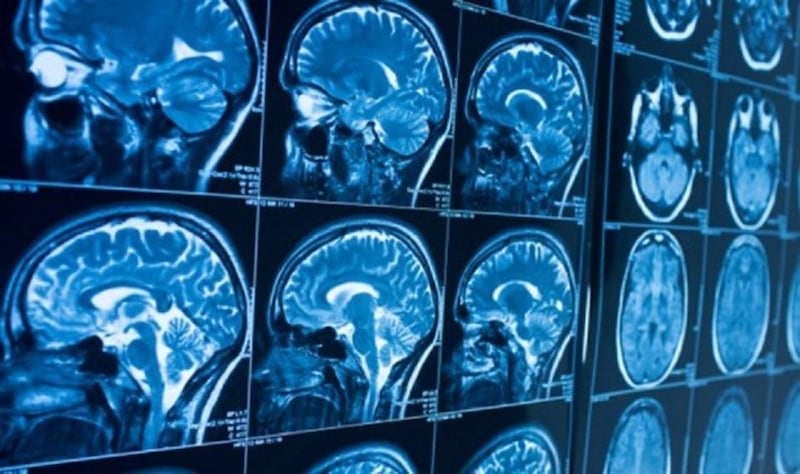

Imágenes de cerebro

Imágenes de cerebro (Redacción médica)

Las imágenes cerebrales de los voluntarios privados de sueño mostraron que se producían lapsos de atención (fallos en la concentración y la respuesta) que anticipaban la expulsión de líquido cefalorraquídeo (LCR).